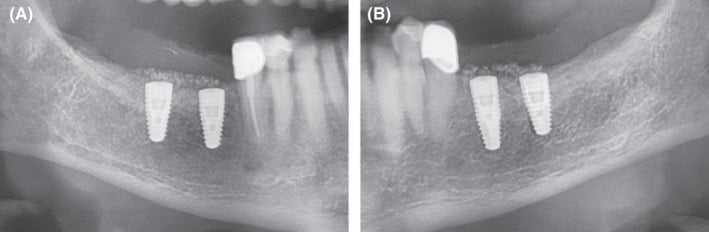

Figure 11.

Clinical situation after prosthetic treatment in the third and fourth quadrant. A, Clinical result on the allogeneic site after prosthetics. Fixed mucosa was increased by Kazanjian vestibuloplasty to 5‐6mm. B, Similar clinical situation on the autologous bone plates site

Figure 12.

Extracts from OPG: Radiological situation after prosthetic treatment. A, Allogeneic site with good integration of the implants and no crestal bone loss and well‐integrated relining layer. B, Autologous site showing good integration, no bone loss and well‐integrated relining layer on the autologous site